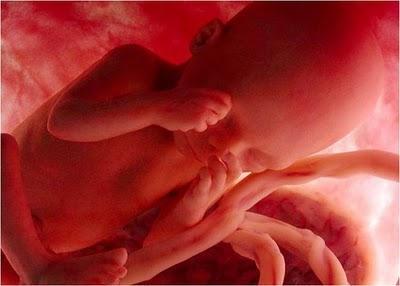

Las imágenes utilizadas en esta presentación son parte del documental "En el vientre materno" producido por National Geographic.

Son imágenes obtenidas a través de una micro-cámara introducida en el útero de una gestante. Gracias a las modernas técnicas fotográficas es posible acompañar el fascinante proceso de gestación de un bebé.

A LA 16ª SEMANA DE GESTACIÓN YA CASI TODOSSUS ÓRGANOS ESTÁN DESARROLLADOS.

LOS OJOS AÚN ESTÁN CERRADOS, SUS MANOS Y PIE COMIENZAN A MOVERSE, AUNQUE SU MADRE CASI NO LO PERCIBE AÚN.